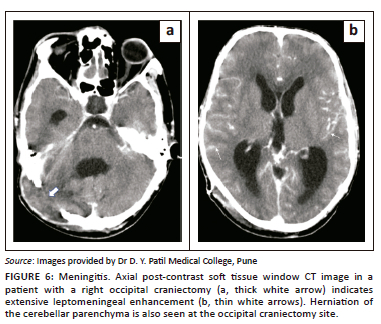

Infections

Post-craniotomy infections are a relatively uncommon complication, with an incidence of less than 1% described in the literature, and usually present as extradural abscesses, meningitis (Figure 6), subdural empyema and parenchymal abscesses.11,12 The infection usually begins in the subcutaneous plane at the surgical site and extends to the deeper tissues. Contrast imaging plays an important role in diagnosing involvement of the bone flap, extra-axial cerebrospinal fluid (CSF) spaces, meninges and brain parenchyma.